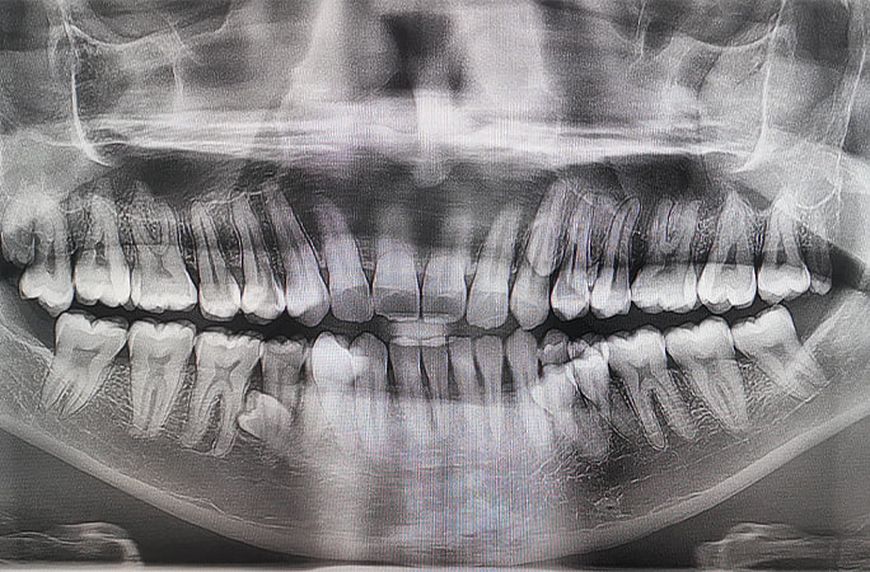

Наличие такого количества зубов подтвердили два стоматолога, которые обнаружили, что у него есть еще два непрорезавшихся. Пратаб Мунианди работает инженером в нефтегазовой отрасли и воспитывает сына. Рекордсмен рассказал, что впервые обратил внимание на зубы в 2021 году во время семейного чаепития. По словам Пратаба, тогда он пошутил с родными, что, похоже, у него растут дополнительные зубы. Вместе они решили их сосчитать и обнаружили 38. Впоследствии рентгеновское обследование показало, что в челюсти есть еще четыре зуба, которые на тот момент не прорезались. Отмечается, что зубы растут необычно, в два ряда.